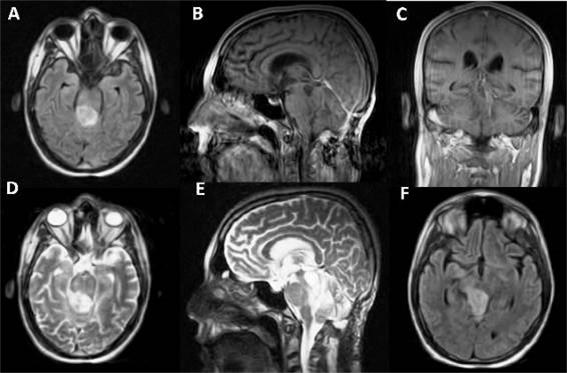

Se decidió un abordaje supracerebeloso infratentorial a la lesión tumoral, con apoyo endoscópico en posición semisentado. (Figura 2)

Cumplió profilaxis antibiótica con cefazolina 3 g en las primeras 24 h. Se le realizó craniectomía de fosa posterior, para facilitar abordaje supracerebeloso infratentorial, con introducción de lente de endoscopia de 0° inicialmente y luego de 30° (Karl Storss, Alemania); se constató lesión friable y sangrante, la cual se aspiró con facilidad. (Figura 3)